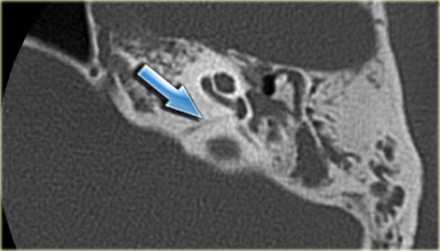

(Слева) На рисунке в аксиальной плоскости показаны признаки аплазии улитки, включая уменьшение внутреннего слухового канала (ВСК) с отсутствием улитковою нерва, улитки; с мальформацией преддверия и полукружного канала, уплощением переднею колена ЧH VII.

(Справа) При аксиальной МРТ SPACE у четырехмесячной девочки с врожденной НСТУ отсутствует улитка. Определяется глобулярная аномалия преддверия и горизонтального полукружного канала. В коротком и узком внутреннем слуховом канале находятся преддверный и лицевой нервы. Улитковый нерв не визуализируется.

1. КТ при аплазии улитки:

• КТ в костном окне:

о Улитка: отсутствует с одной или с обеих сторон

о Канал улиткового нерва: отсутствует

о Мыс улитки: гипоплазия, уплощение

о Преддверие и ПКК: мальформация, шаровидная форма, расширение или гипоплазия (часто)

о Водопровод преддверия: обычно норма

о Канал лицевого нерва: аномальный тупой угол переднего колена

о ВСК: обычно гипоплазия

о Среднее ухо: нормальный размер

о Слуховые косточки: норма или мальформация стремечка

о Овальное окно: норма или стеноз/атрезия

о Круглое окно: атрезия

2. МРТ при аплазии улитки:

• Т2 ВИ:

о Улитка и улитковый нерв: отсутствуют

о Преддверие и ПКК: различные нарушения

(Слева) При аксиальной КТ в костном окне у этой же пациентки отсутствует улитка, определяется легкое уплощение мыса улитки.

(Справа) При аксиальной КТ в костном окне у этой же пациентки определяется глобулярная мальформация преддверия и горизонтального полукружною канала. Визуализируется короткий и узкий ВСК. Частично визуализируется переднее колено лицевого нерва, идущее под тупым углом, канал лицевого нерва имеет аномальный ход.